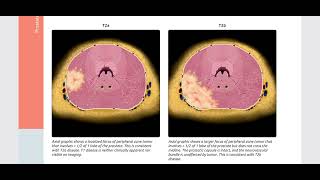

Prostate MRI Introduction Multi-parametric Prostate MRI using PI-RADS v 2.1: an Introduction

Multi-parametric Prostate MRI using PI-RADS v 2.1: an Introduction Prostate MRI: Introduction PI-RADS v2.1 on MRI

Prostate MRI: Introduction PI-RADS v2.1 on MRI Prostate MRI Case Review: A Look at PI RADS 2.0 Terminology